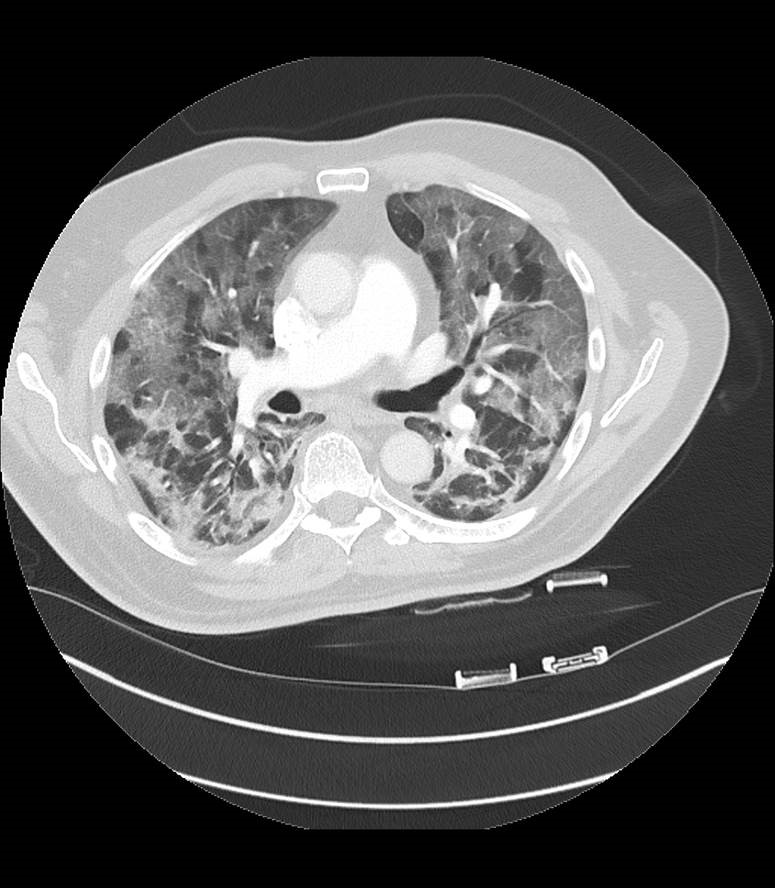

„Die Computertomographie war vor allem in den ersten Monaten der Pandemie bei der Diagnose der Patienten mit Verdacht auf eine Corona-Erkrankung eine wertvolle Hilfe“, sagt Prof. Dr. Dierk Vorwerk, Leiter des Zentrums für Radiologie und Neuroradiologie im Klinikum Ingolstadt. Damals – vor ziemlich genau einem Jahr – waren die Testmöglichkeiten beschränkt, Schnelltests gab es noch nicht wie in der jetzigen Form. Ein CT der Lunge konnte also schnell Auskunft darüber geben, ob eine Corona-Infektion vorlag. „Bei etwa der Hälfte der Betroffenen ließen sich die Anzeichen auf eine Covid-19-Infektion bereits ab dem dritten Tag nach Ansteckung feststellen – und das innerhalb von wenigen Sekunden.“ Trotzdem sei die CT-Aufnahme der Lunge niemals ein Ersatz für einen Labortest gewesen. Mit dem CT lassen sich lediglich die für Covid-19 typischen Veränderungen feststellen. „Ein Abstrich findet immer zusätzlich zur CT-Untersuchung statt“, so Prof. Vorwerk. Ist ein Patient an Covid-19 erkrankt, zeigt sein CT-Bild häufig wolkenartige Verdichtungen in den Außenbereichen der Lunge. Diese Milchglastrübungen seien typisch – aber nicht spezifisch – für die Krankheit.

Das Gerät setzt den Fokus speziell auf Untersuchungen der Lunge und eignet sich daher bestens für den Einsatz an Patienten mit Covid-19-Verdacht. Es wurde räumlich getrennt von anderen Geräten und Untersuchungszimmern in den Räumlichkeiten der Notfallklinik installiert. Die Vorbereitung der Räumlichkeiten, Umbau und technische Ausrüstung wurden von den beteiligten Abteilungen vor einem Jahr in Rekordzeit realisiert. Von der Radiologie betrieben, werden Untersuchungen am Gerät seitdem vom Notfallzentrum, der Infektionsstation und der Anästhesie angefordert – überall dort, wo Corona-Patienten behandelt werden. „Insgesamt wurden so innerhalb der vergangenen zwölf Monate über 3.200 Patienten an diesem Gerät untersucht“, sagt Christine Gunselmann, medizinisch-technische Radiologieassistentin, kurz: MTRA, am Klinikum Ingolstadt. Eine beachtliche Leistung der Ärzte und MTRAs, wenn man bedenkt, dass die sonstigen Untersuchungen ganz normal weiterliefen. Das Corona-CT wird vor allem genutzt, um eine Lungenbeteiligung bei Covid-19 festzustellen und von einer Lungenembolie zu unterscheiden sowie um den Verlauf der Krankheit zu untersuchen. „Wir können damit nachvollziehen, wie sich die Krankheit entwickelt und wie stark die Lunge beschädigt ist“, sagt Vorwerk.